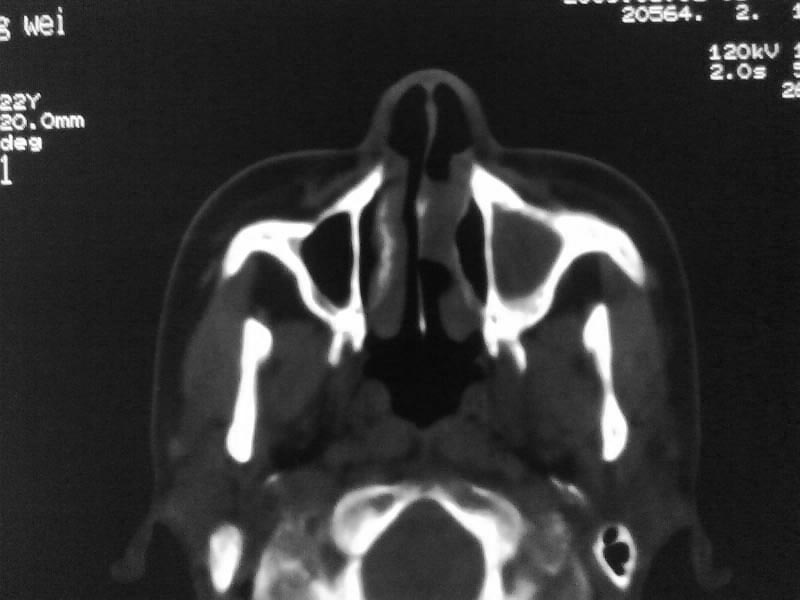

以下是引用zjzjr在2009-5-3 9:59:00的发言:[br]左侧鼻腔息肉、左侧筛窦、上颌窦炎症。双侧下鼻甲粘膜肥厚。

以下是引用随光逐影在2009-5-3 13:02:00的发言:[br]1)左侧鼻腔新生物(息肉可能)。2)左侧上颌窦及左侧筛窦炎症。3)双侧下鼻甲黏膜肥厚。